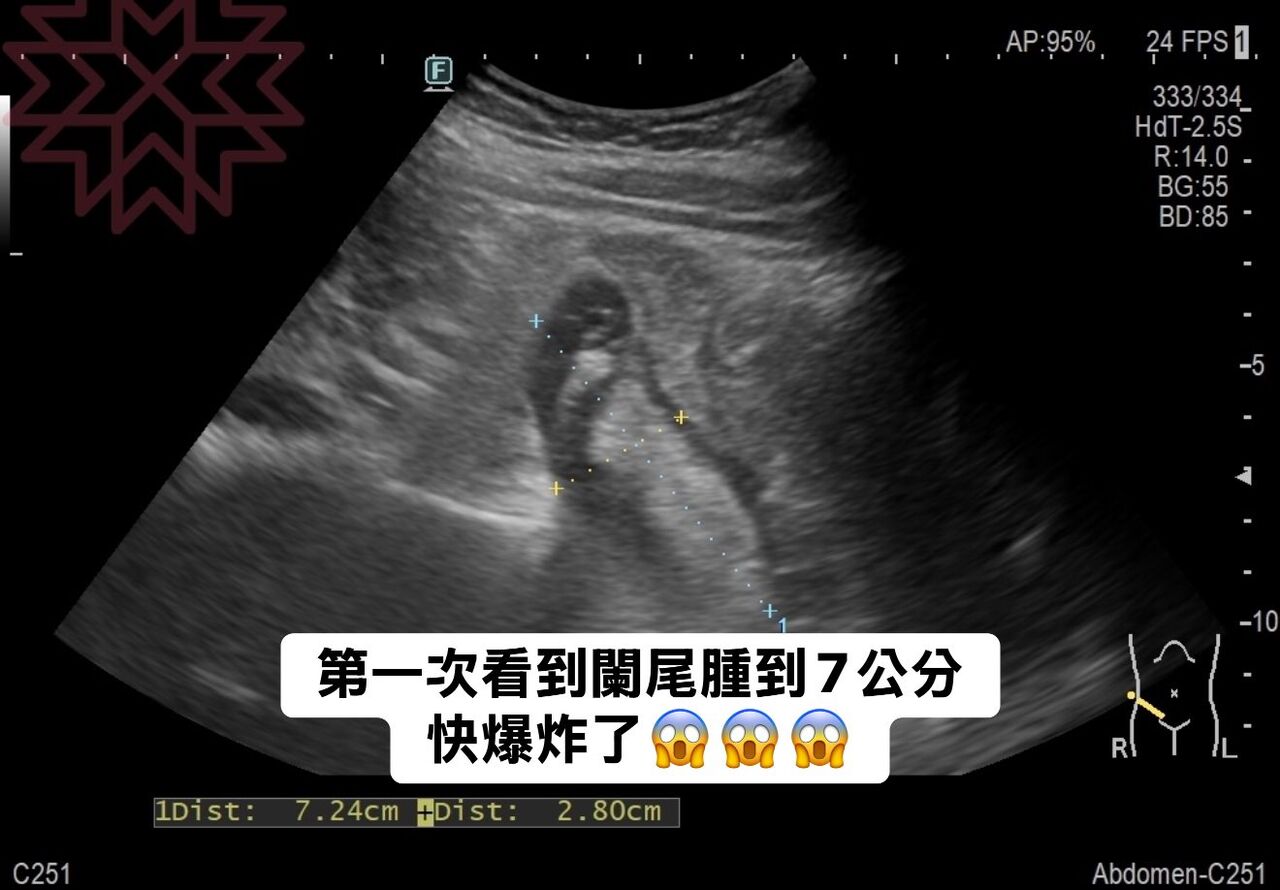

▲醫師說,「第一次看到闌尾腫到7公分,快爆炸了。」(圖/翻攝林相宏臉書)

禾馨民權健康管理診所院長林相宏分享,一名40歲女性胃超痛看診,結果一照超音波,「天啊,我還第一次看到闌尾腫成這樣(7公分),快爆炸了」,難怪會痛成這樣。

林相宏提到,「天啊!我還第一次看到闌尾腫成這樣(7公分),難怪病患會痛成這樣,趕快轉診手術,發現闌尾炎已經腫到快要爆裂,不過好險及時,還沒有腹膜炎。」